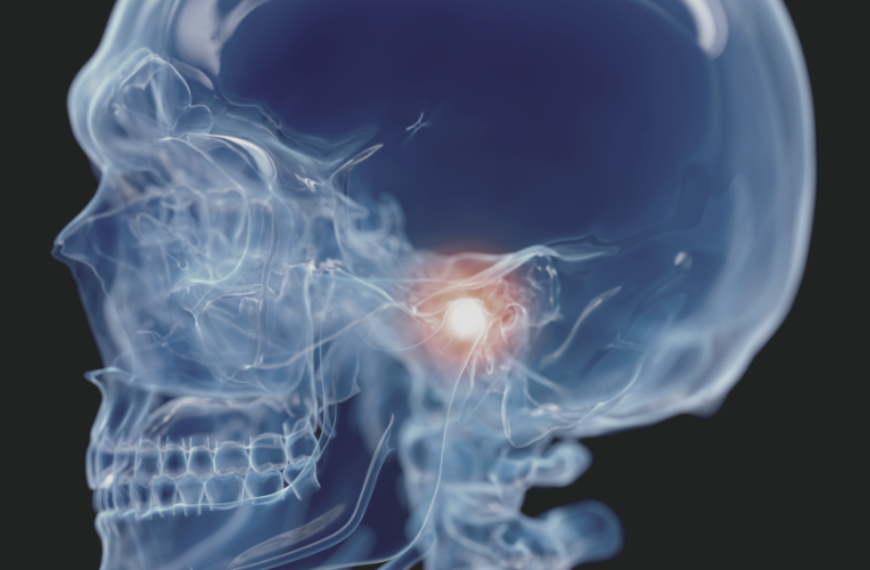

턱관절 장애

입을 벌리기가 어렵고 아프거나 턱을 움직일 때 귀 부근에서 딱딱하고 소리가 난다면 우선 턱관절 장애를 의심해 보아야 합니다.

• 턱관절 장애

턱관절 장애란,

턱관절 장애는 턱관절과 주변 관련 구조물에 발생하는 질환을 모두 포함하는 용어입니다. 턱관절 장애는 턱관절의 염증 또는 탈구 등으로 인해 소리가 나거나 통증이

느껴지며 입을 벌리는데 장애가 있는 질환을 말합니다.

음식물을 씹을 때 턱 주변에서 느껴지는 통증, 입을 벌릴 때 '딱'소리가 나거나

통증으로 입을 벌리지 못하는 것 모두 턱관절 장애의 대표적인 증상입니다.